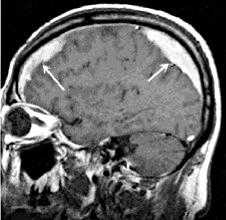

![МРТ головного мозга. Массивная двухсторонняя хроническая субдуральная гематома.]()

Решающими методами в диагностике субдуральной гематомы являются КТ и МРТ головного мозга. В диагностике острых гематом предпочтение отдается КТ головного мозга, которая в таких случаях выявляет однородную зону повышенной плотности, имеющую серповидную форму. С течением времени происходит разуплотнение гематомы и распад кровяных пигментов, в связи с чем через 1-6 нед. она перестает отличается по плотности от окружающих тканей. В подобной ситуации диагноз основывается на смещении латеральный отделов мозга в медиальном направлении и признаках сдавления бокового желудочка.

![КТ головного мозга. Подострая субдуральная гематома справа]()

При проведении МРТ может наблюдаться пониженная контрастность зоны острой гематомы; хронические субдуральные гематомы, как правило, отличаются гиперинтенсивностью в Т2 режиме. В затруднительных случаях помогает МРТ с контрастированием. Интенсивное накопление контраста капсулой гематомы позволяет дифференцировать ее от арахноидальной кисты или субдуральной гигромы.